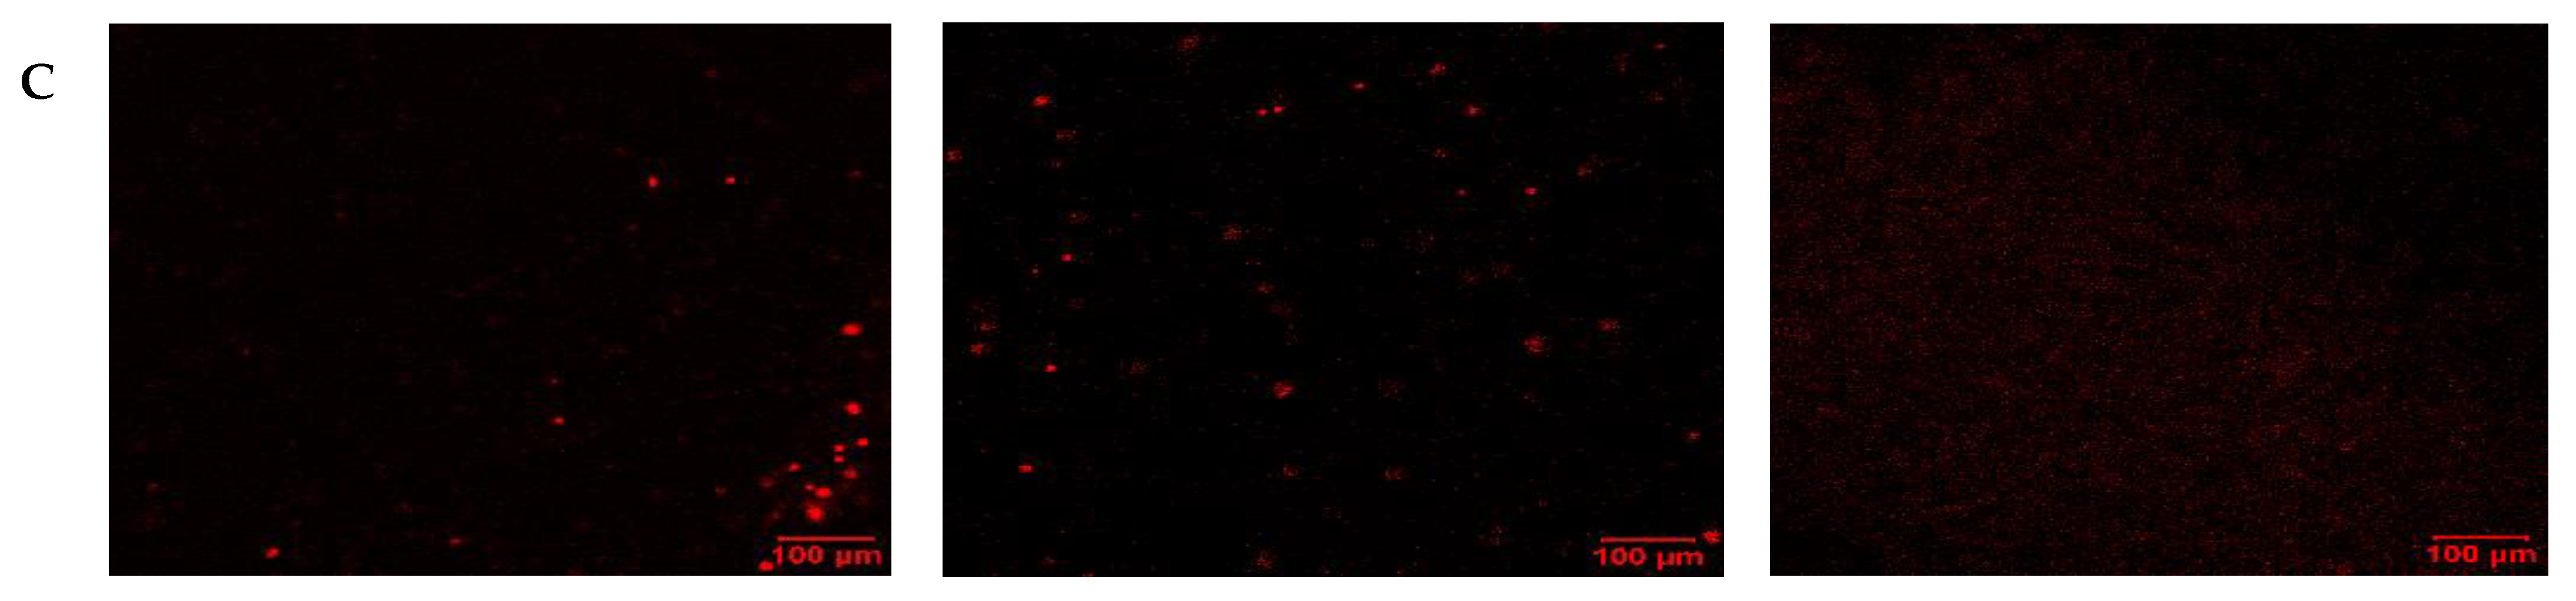

To visualize the apoptotic cells, confocal laser scanning microscopy (LSM) was employed. In this case, single treatments with thymoquinone and carboplatin were compared with untreated control cells. Under normoxic conditions (Figure 6), carboplatin induced very little apoptosis, as evidenced by minimal green staining. Interestingly, with thymoquinone treatment, an absence of nuclear stain and blue stain bleeding into the media was evident. In comparison, under hypoxic conditions (Figure 7), the control showed higher levels of apoptosis and necrosis, reflecting the effect of the harsh hypoxic conditions on untreated cells. Both with carboplatin and thymoquinone treatment, a relatively greater number of cells were seen to be apoptotic, and more were also necrotic compared with the normoxic. Furthermore, with thymoquinone, not all the cells were lysed, as evidenced by the presence of nuclear stain.

Figure 7. Confocal LSM image of OECM-1 cells on treatment with carboplatin, and thymoquinone in hypoxic conditions, with nuclear stain (A), apoptotic stain (B) and necrotic stain (C).